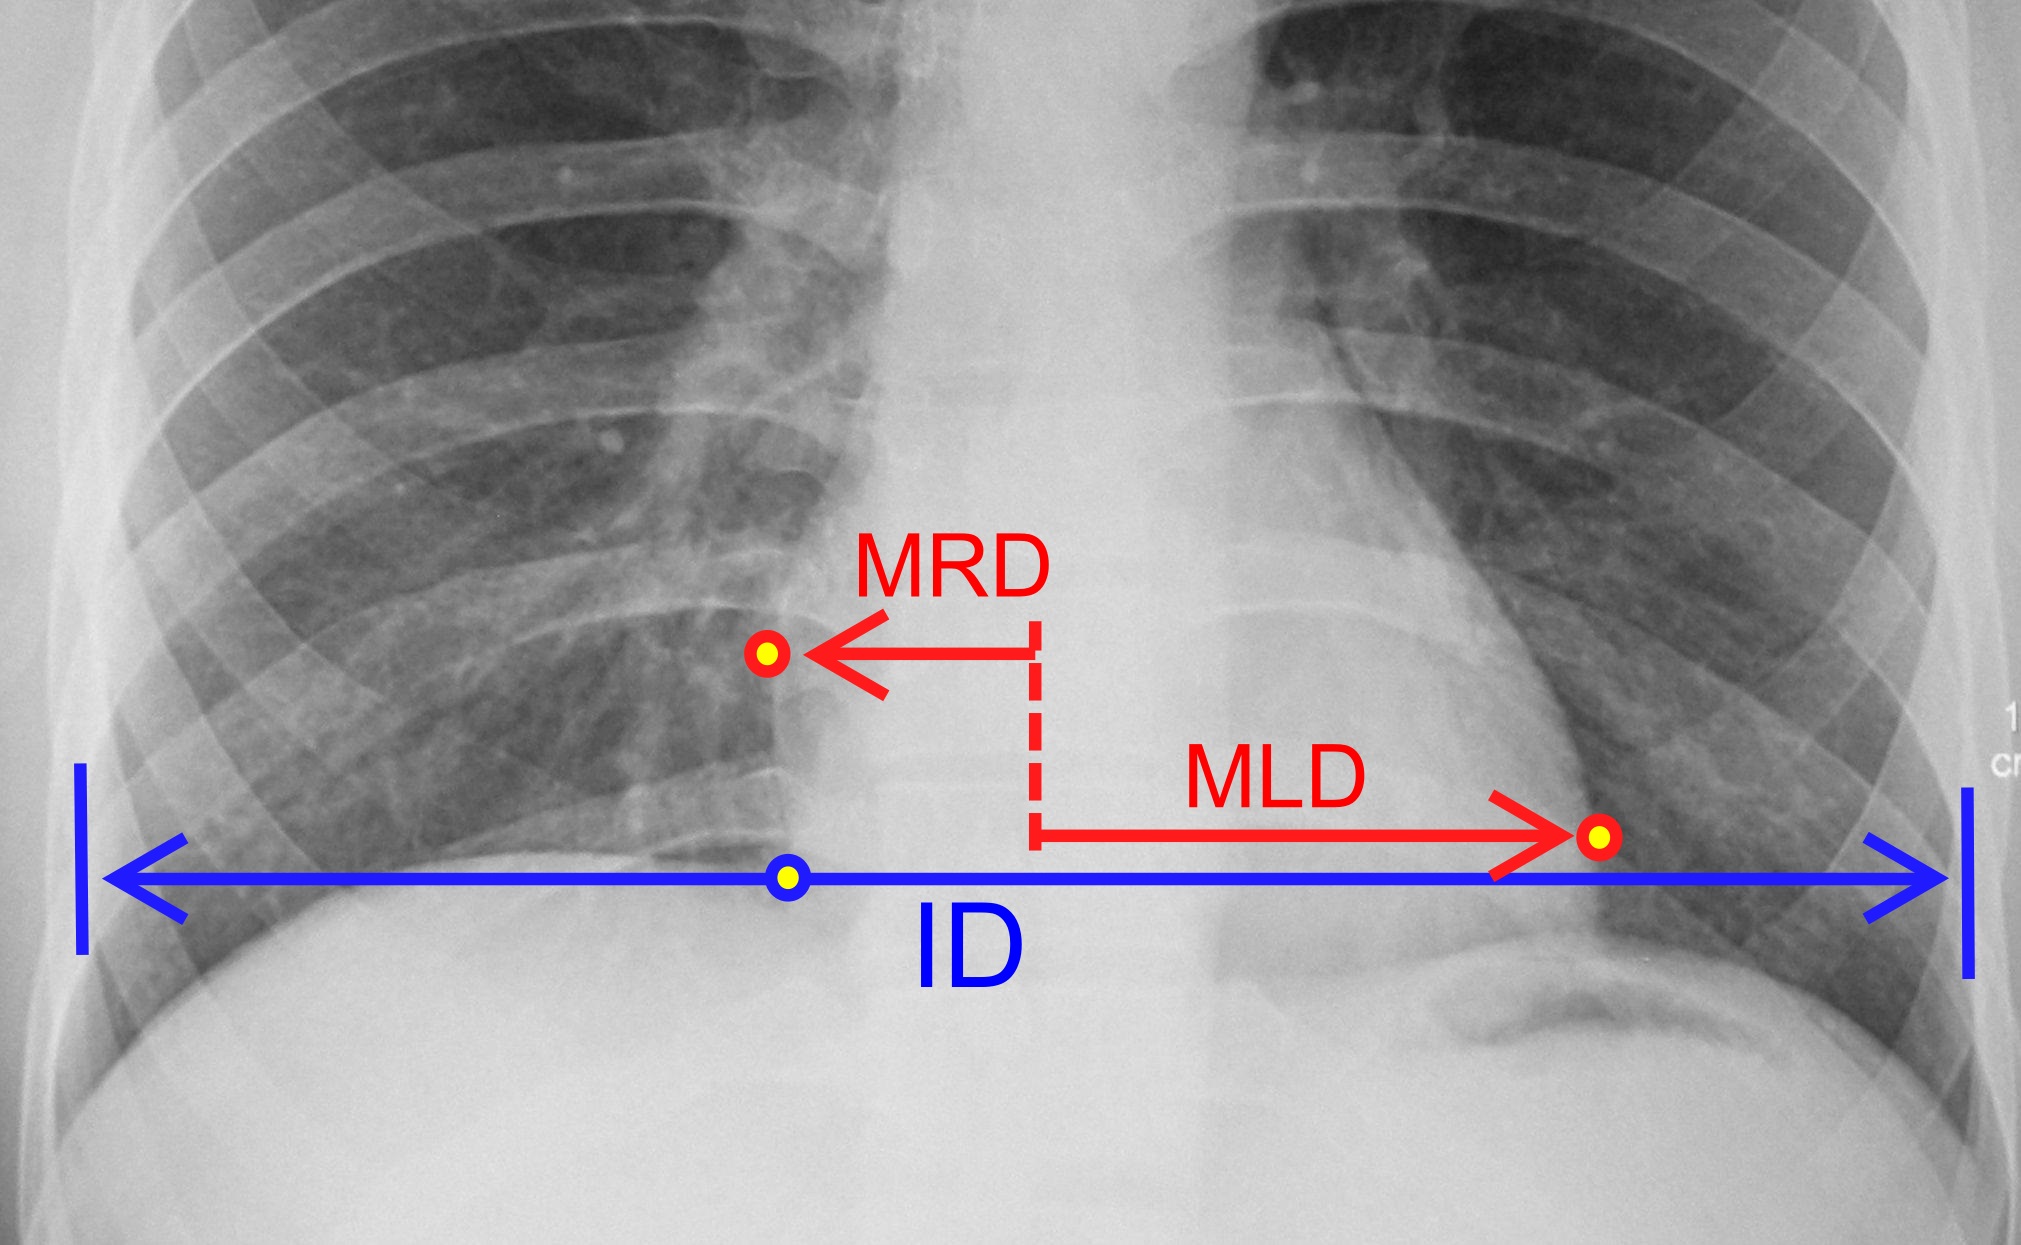

where:[23]

MRD = midline에서 심장 오른쪽 경계까지의 가장 큰 수직 직경

MLD = midline에서 심장 왼쪽 경계까지의 가장 큰 수직 직경

ID = 오른쪽 반쪽 횡격막 수준에서 가슴의 내부 직경]]

- '''흉부 X-레이''': X-ray 영상은 폐와 심장의 상태를 시각화하는 데 도움이 된다. X-레이에서 심장이 비대해진 경우, 일반적으로 그 원인을 찾기 위해 다른 검사가 필요하다. X-레이에서 유용한 측정은 심흉비로, 이는 심장의 가로 직경을 흉곽의 가로 직경과 비교한 것이다.[24] 이 직경은 흉부의 가장 넓은 지점을 사용하여 폐 폐흉막까지, 측면 피부 경계가 아닌 PA 흉부 X-레이에서 측정된다. 비율이 50%를 초과하면 병리가 의심된다.[25] 이 측정은 1919년에 군 신병을 선별하기 위해 처음 제안되었다. 이러한 X-레이를 심장 건강 평가에 사용하는 새로운 접근법은 심장 면적과 흉부 면적의 비율을 취하며, 이를 2차원 심흉비라고 부른다.[26]